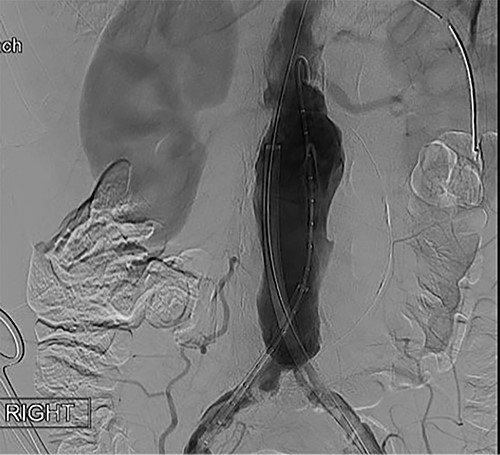

To obtain vascular access, bilateral cutdown technique was used to dissect the common femoral arteries. The femoral arteries were cannulated, the patient heparinized, and an arteriogram obtained (Fig. 2). The main body of the graft was deployed without complication, followed by bilateral iliac limb extensions. The graft was treated with the Molding & Occlusion Balloon (MOB) at all attachment points. Repeat arteriogram demonstrated excellent technical result without evidence of endoleak (Fig. 3). Protamine was administered for reversal of heparin, bilateral groin incisions were closed, and nasogastric tube (NGT) was left in place on low intermittent wall suction. Aspirin/Plavix therapy was continued.

Intraoperative fluoroscopy illustrating successful endovascular aneurysm repair (EVAR).